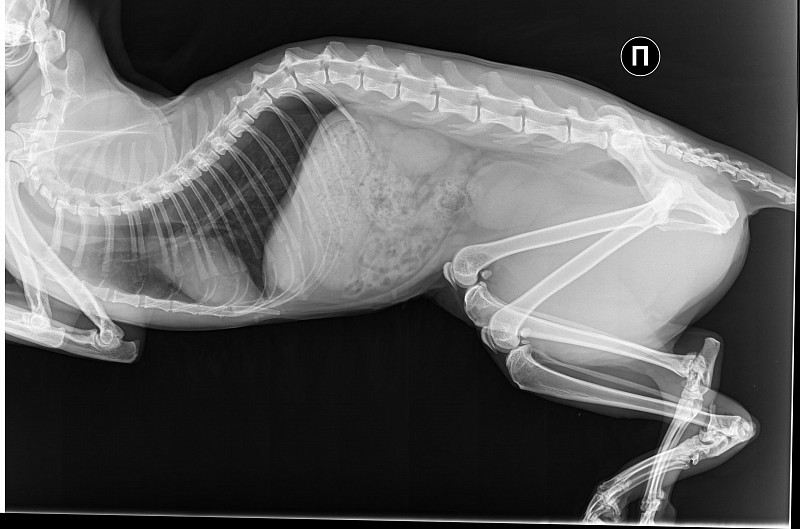

Истончение костей у кошек: причины и решения